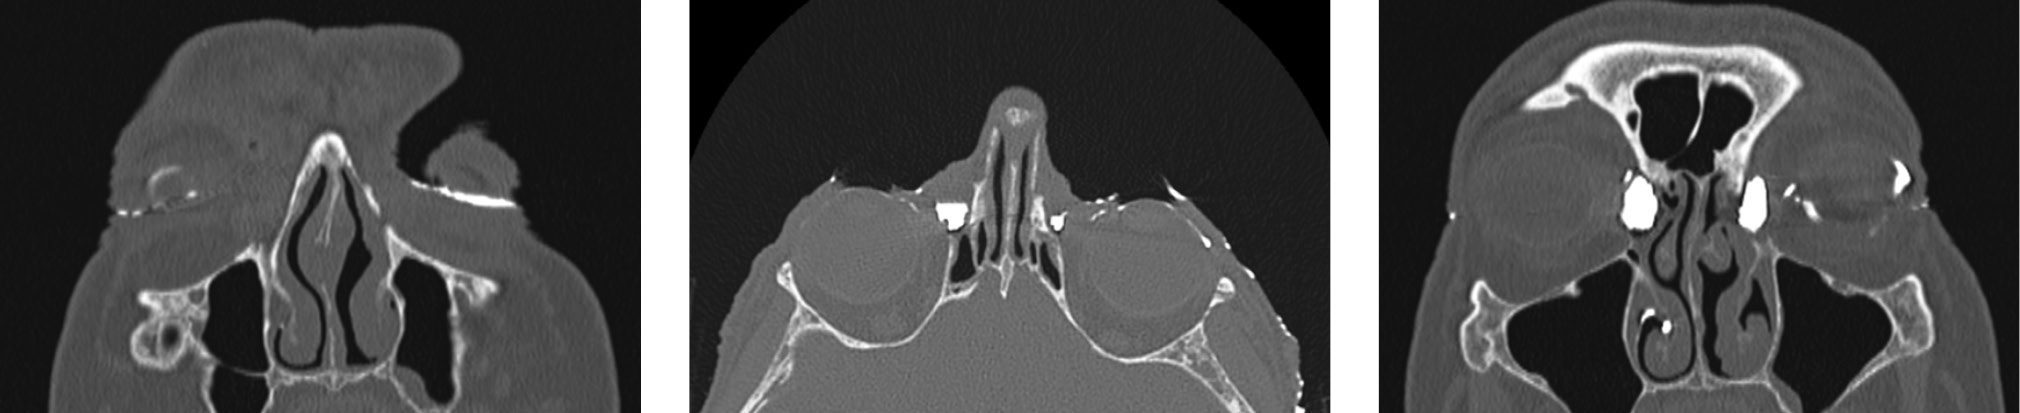

Наиболее распространенной причиной дакриоцистита оказалась ретроградная резекция крючковидного отростка с помощью обратного выкусывателя или при использовании микродебридера в ходе эндоназальной риноантростомии (12 случаев, 31,58 %). Интересно, что повреждение чаще всего было локализовано в области задневерхних отделов НСК, а также в области шейки слезного мешка (рис. 4). Наши данные согласуются с данными литературных источников [1, 2, 4–6, 8, 13, 14, 17].

Рис. 4. Облитерация носослезного протока справа на уровне верхней трети после осуществления ретроградной инфундибулотомии справа. Мультиспиральная компьютерная томография выполнена через 3 мес. после проведенной FESS (стрелки)

Fig. 4. Right nasolacrimal duct obliteration at the level of the upper third after right retrograde infundibulotomy. Multislice computed tomography at 3 months after FESS (arrows)